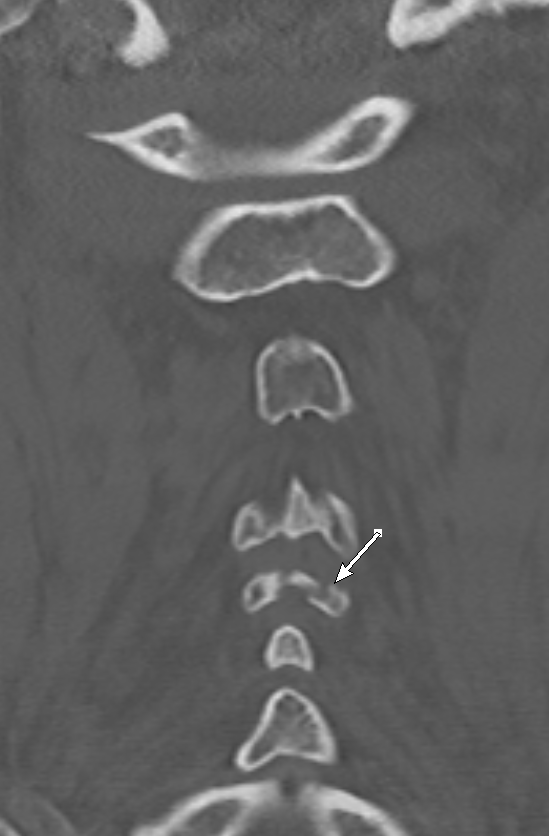

#radres sometimes the finding is in the bottom corner, outside the requested area#easytomiss T4#fracture on a cervical#spine CT#FOAMed#FOAMrad#EMrad#MSKrad#Neurorad@ASER_ERad@NASSspinepic.twitter.com/zYOqyGSaFl